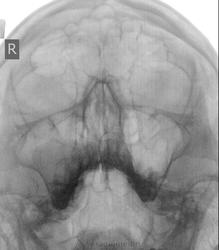

Случай второй: молодой человек 22 лет. от ЛОРа. вроде киста, но может есть что-то с альвеолярным отростком верхней челюсти справа?

Во втором случае больше симпатий в векторе кисты. Мы частенько в таких ситуациях проводим линейную томографию.

Валентин Львович, нет там условий производить линейные томограммы. Даже стола рентгеновского нет, только стойка-вертиграф. Да и аппарат палатный, правда хороший. Эти снимки из все той же "частной лавочки")). Подозрениями поделилась с направившим ЛОРом, направили его сразу на КТ, благо в СПб их много и они доступны. В заключение вынесла кисту. Мне больше инетерсно, не одонтогенной ли она природы? и что это с альвеолярным отростком верхей челюсти?

в пазухе киста типичная, а челюсти - ну даже если гранулема, то это явн не к нам